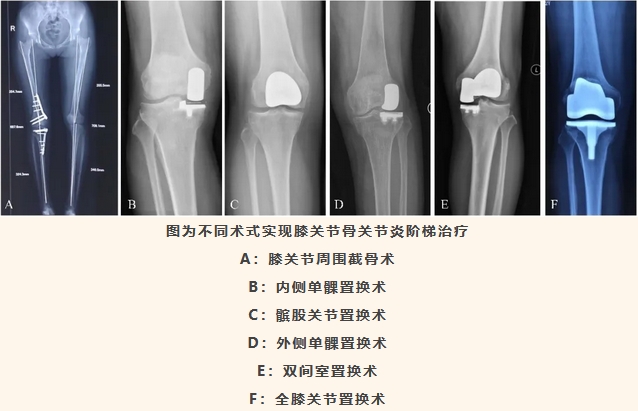

近年来,北京积水潭医院矫形骨科不断探索和完善膝关节骨关节炎的阶梯治疗,已成功建立了基础运动康复,药物治疗,关节腔内注射疗法,关节周围截骨,膝关节内侧单髁置换术,膝关节外侧单髁置换术,膝关节髌股关节置换术,膝关节双间室置换术,全膝关节置换术治疗膝关节骨关节炎的全套精准阶梯化治疗方案,实现了根据患者骨关节炎阶段给予患者最佳的手术技术方案,而不是仅仅拘泥于一两种手术技术,真正做到以疾病特点为中心而不是以技术为中心。同时随着机器人辅助手术在矫形骨科的全面开展,矫形骨科在个性化精准治疗更进一步,不仅在术式选择上更为准确,更是国内率先实现个性化定制膝关节假体的团队,并提出了解析型关节置换术新理念,在诊疗理念及技术水平均处于国际领先水平。